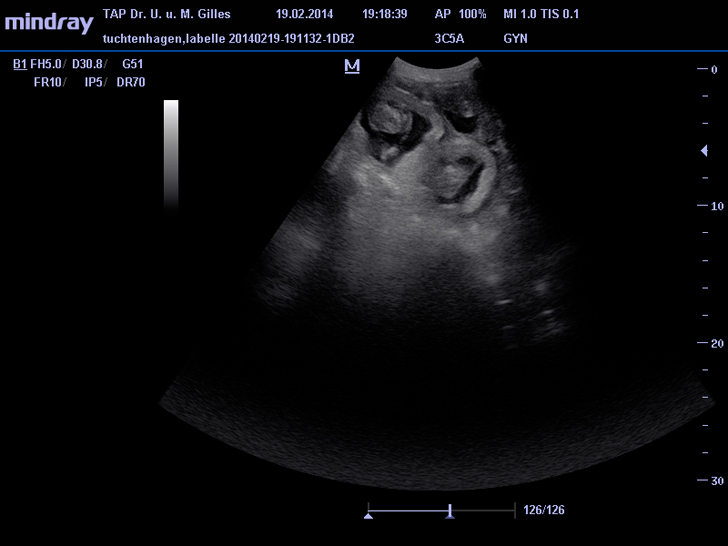

Neuer Ultraschall vom 19.02.2012 (42. Tag):

Alle kleinen Hunde-Embryos leben und haben sich prächtig entwickelt.

ZZt. sind sie schon ca. 7 cm groß.